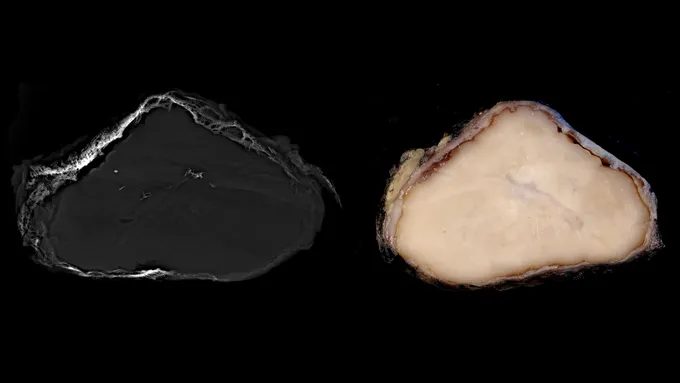

Это доброкачественное новообразование размером с бильярдный шар (показано на фотографии) выглядит обманчиво злокачественным. Новые четкие рекомендации, помогающие врачам распознавать его, могут помочь пациентам избежать вредного лечения. Джон Гросс, Эндрю Розенберг и Грег Чарвилл

У нее есть признаки, которые легко можно принять за раковую ткань. Но новый тип опухоли с мягкими внутренностями, покрытыми твердой костной коркой, на самом деле доброкачественный.

Исследователи назвали опухоль OSET (оссифицирующая веретенообразная и эпителиоидная опухоль) в честь ее внешнего вида и двух типов клеток, которые она содержит, — оба из которых нетипичны для опухолей, покрытых костью. Это открытие позволило врачам провести правильное лечение: удалить опухоль и избежать химиотерапии. Ни один из пациентов, участвовавших в исследовании, не сообщил о возобновлении роста после операции.